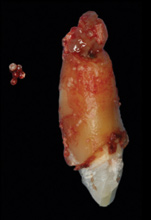

Based on the single extraction socket roadmap developed by El Chaar and colleagues, the socket of tooth No. 8 was diagnosed as Grade III and would require initial treatment that included the extraction of failing tooth No. 8 followed by simultaneous guided bone regeneration and soft-tissue augmentation by means of a rotated palatal pedicle flap (Figure 8 through Figure 11).27,28 The principles of and guidelines for both the ridge augmentation and rotated pedicle flap have been described in the literature and will not be focused on in this case report.27-30 The patient was temporized with a bonded Maryland bridge that was adjusted to avoid creating pressure on the tissue during healing (Figure 12).

8. Tooth No. 8 with diagnosis of Grade III socket, requiring extraction followed by guided bone regeneration and a rotated pedicle flap to gain hard and soft tissue for future implant placement.

Figure 8

9. Tooth No. 8 with diagnosis of Grade III socket, requiring extraction followed by guided bone regeneration and a rotated pedicle flap to gain hard and soft tissue for future implant placement.

Figure 9

10. Tooth No. 8 with diagnosis of Grade III socket, requiring extraction followed by guided bone regeneration and a rotated pedicle flap to gain hard and soft tissue for future implant placement.

Figure 10

11. Tooth No. 8 with diagnosis of Grade III socket, requiring extraction followed by guided bone regeneration and a rotated pedicle flap to gain hard and soft tissue for future implant placement.

Figure 11